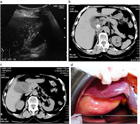

1. 急性胆嚢炎の原因の90~95%は胆嚢結石であり、結石の嵌頓による胆嚢管閉塞と胆嚢内胆汁うっ滞に引き続き、胆嚢粘膜障害が起こり、炎症性メディエーターの活性化が引き起こされる。

1. 急性無石胆嚢炎は急性胆嚢炎の3.7~14%を占め、その危険因子は、手術、外傷、長期のICU滞在、感染症、熱傷や経静脈栄養などである。